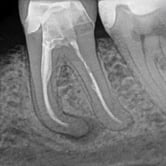

Pulpitis Irreversible

La pulpitis irreversible es una inflamación severa de la pulpa dental que no se puede curar por sí sola, a menudo debido a una caries profunda o una lesión grave.

Los pacientes suelen sentir dolor intenso y prolongado, especialmente con estímulos calientes.

La única solución es el tratamiento de conducto para salvar el diente. Sin tratamiento, la pulpa morirá y puede llevar a una infección.